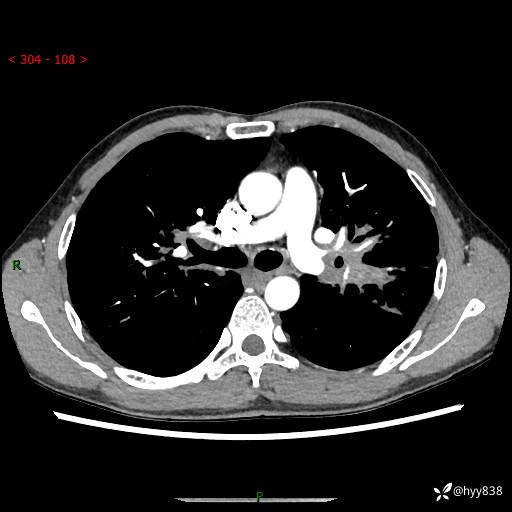

中年男性,咳嗽咳痰1月余。细看:肺、肺门、气管,貌似都有问题---(有结果)

现病史:患者于1个月前受凉后出现间断性咳嗽,伴白色泡沫样痰,无发热寒战、咯血、胸痛胸闷、恶心呕吐、呼吸困难等特殊不适,起初未予特殊处理,后患者就诊当地中医医院,查胸部CT提示支气管炎并双肺感染性病变,经抗感染(哌拉西林舒巴坦),止咳化痰(溴己新、三拗片)等治疗后,患者自诉咳嗽咳痰症状较前缓解,未诉发热等其他特殊不适,近期复查CT提示“肺部感染灶未见消退,双侧肺门增大,双肺散在小结节”,今为求进一步诊治,前来我院就诊,门诊以“肺部感染”收住入院。 患者自起病来精神、食欲、睡眠尚可,大小便正常,体力、体重无明显变化。

胸部CT平扫+增强(两期)